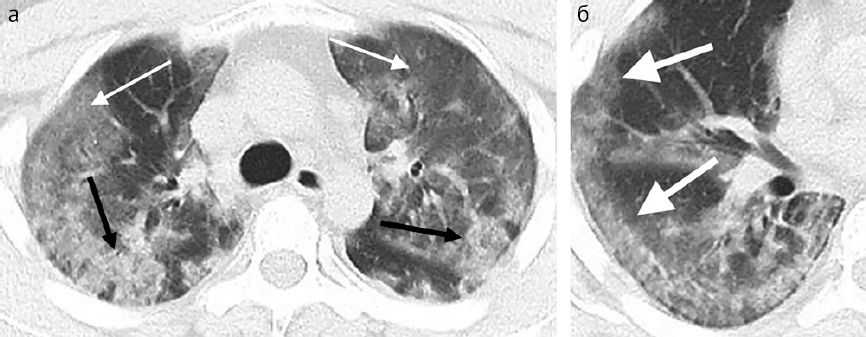

Из 18 пациентов с повышением плотности легочной ткани у 16 изменения были двусторонними, а у двух — односторонним ( у обоих было поражено правое легкое).Суммарный балл по «шкале степени тяжести поражения легкого» варьировался от 0 (при трех нормальных КТ-исследованиях) до максимум 19 со средним баллом 9,9. Пациент с наивысшим баллом тяжести поступил в отделение интенсивной терапии (рис. 1)..

Рисунок 1

29-летний мужчина с неизвестным эпидемиологическим анамнезом, поступил с жалобами на лихорадку, кашель и был сразу направлен в отделение интенсивной терапии. (a) Аксиальный тонкосрезовый КТ-скан без введения контрастного препарата демонстрирует диффузные области уплотнения по типу «матового стекла» сливного характера с двух сторон (белые стрелки) и зоны консолидации (черные стрелки). (б) Аксиальный КТ-скан без введения контрастного препарата показывает, что изменения в правой средней и нижней долях имеет тенденцию к периферической локализации (стрелки).